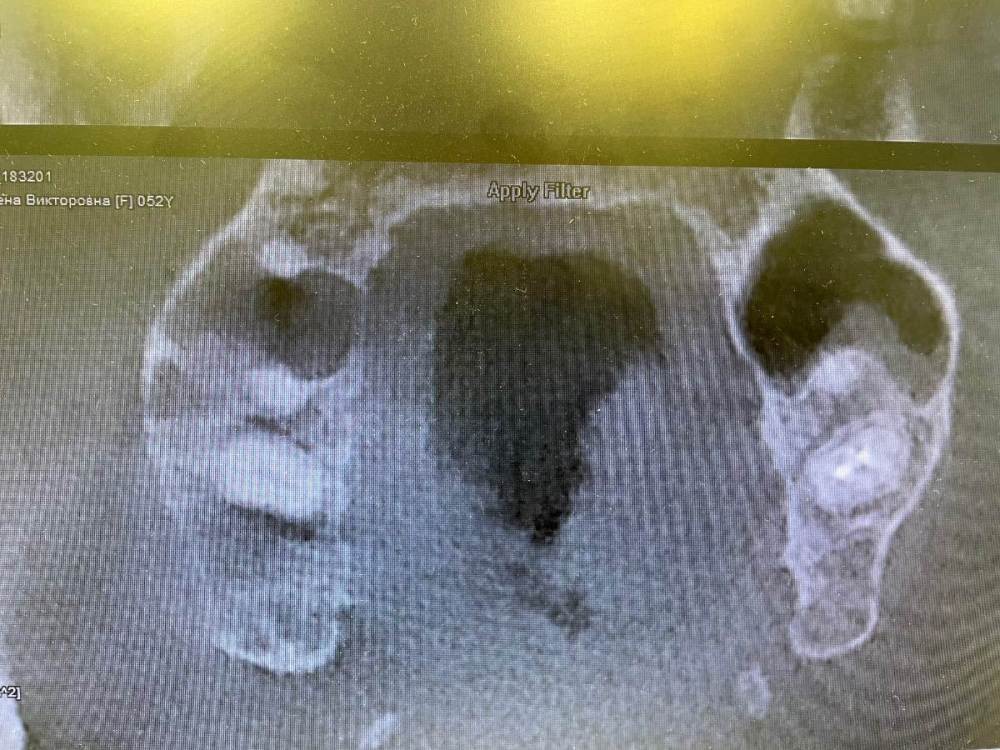

Кирилл Якимов Опубликовано 5 мая, 2022 Поделиться Опубликовано 5 мая, 2022 Добрый день, дорогие коллеги! Я начинающий врач, очень нужна конструктивная критика) 2.7 зуб, каналы лечили несколько лет назад(пациентка точно не помнит). Зуб не беспокоит. Сделал прицельные снимки + КТ. Есть очаг перирадикулярной деструкции+гуттаперча за апексом+резорбция. Принял решение зуб перелечить. Убрал старую пломбу и кариес, гутта в каналах мягкая, распломбировал довольно быстро Profile 25.06 25.04 и желтый Mtwo со стеночек+активация гипохлорита 3% U-file 15 стальным. Из-за апекса гуттаперчу вытащил H-file. В первый визит расширил до 70 K-file. Длина обеих каналов 18мм. Оставил кальций на 2 недели. Коллега микроскопист говорит, что нужно делать пробку МТА, дальше обтурация гибридной методикой, затем коронка и контрольное КТ через 6 мес. Подскажите пожалуйста, как и чем все таки лучше пломбировать такой зуб и какой наиболее вероятный прогноз? Кто что думает, в чем может быть причина такой резорбции? Ссылка на комментарий